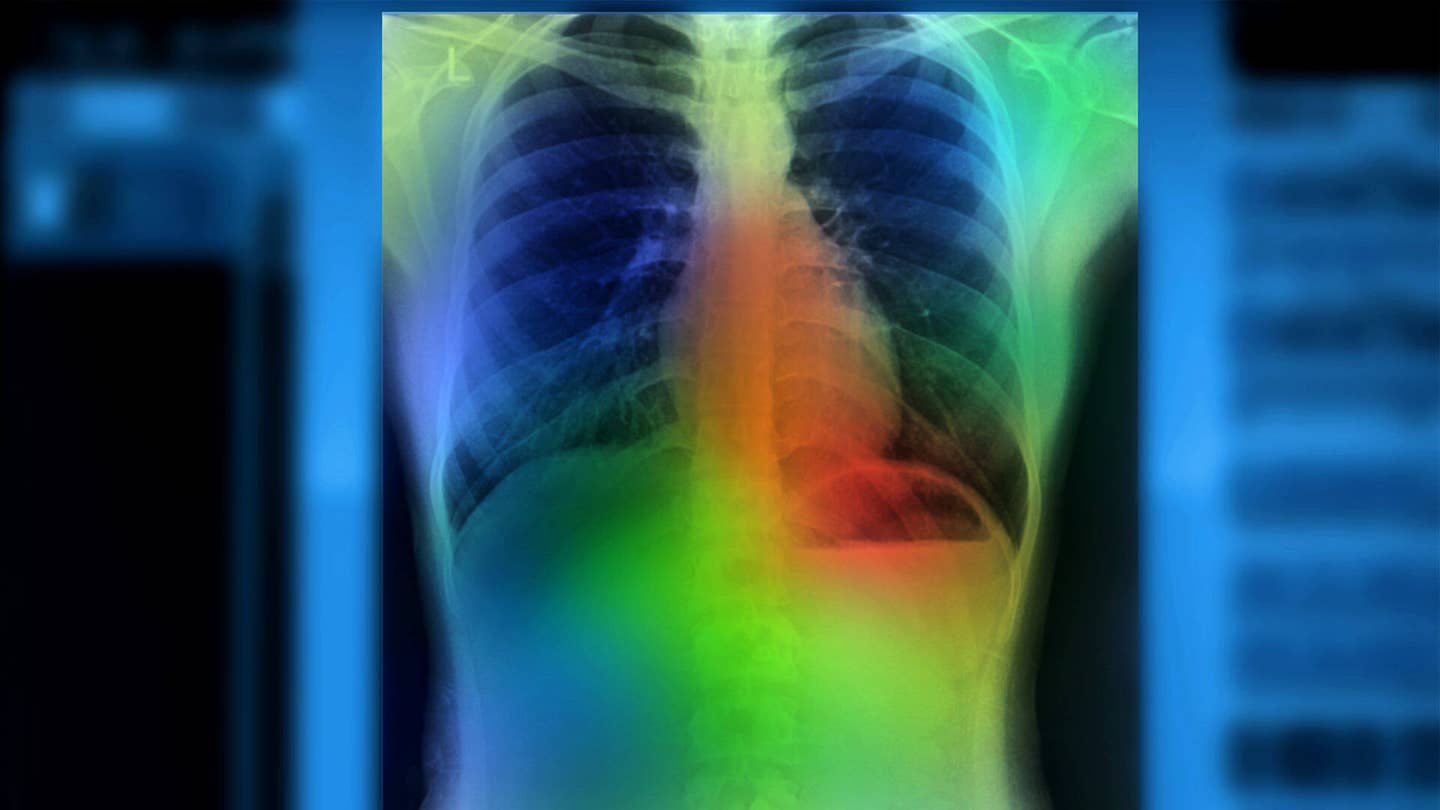

Image Credit: Zapp2Photo / Shutterstock.com